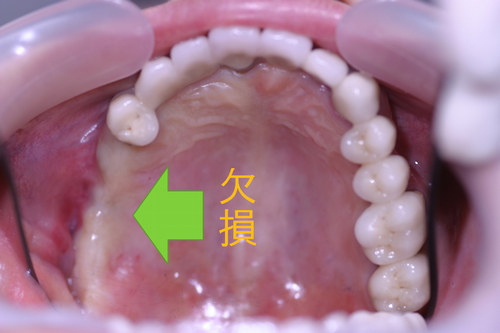

この患者様は、右上の奥歯の歯茎から出血してくるとのことで来院されました。歯周組織検査とレントゲンで診断を行った結果、重度の歯槽膿漏が認められ、保存不可能の為、抜歯になると伝えたところ、入れ歯は絶対に嫌だと言われたので、インプラント治療となりました。CT撮影を行ったところ、上顎洞底までの距離が3ミリ程度しかなかったのですが、骨が固く、フィクスチャーの一次固定が良好だったので、開窓法による上顎洞底挙上術とフィクスチャーの埋入を同時に行いました。約10カ月後に二次手術を行い、上部構造をセットしました。また、右下の臼歯部のブリッジにも大きな二次カリエスが認められ、7番の遠心根が抜歯になり、6番、7番にインプラント治療をしました。